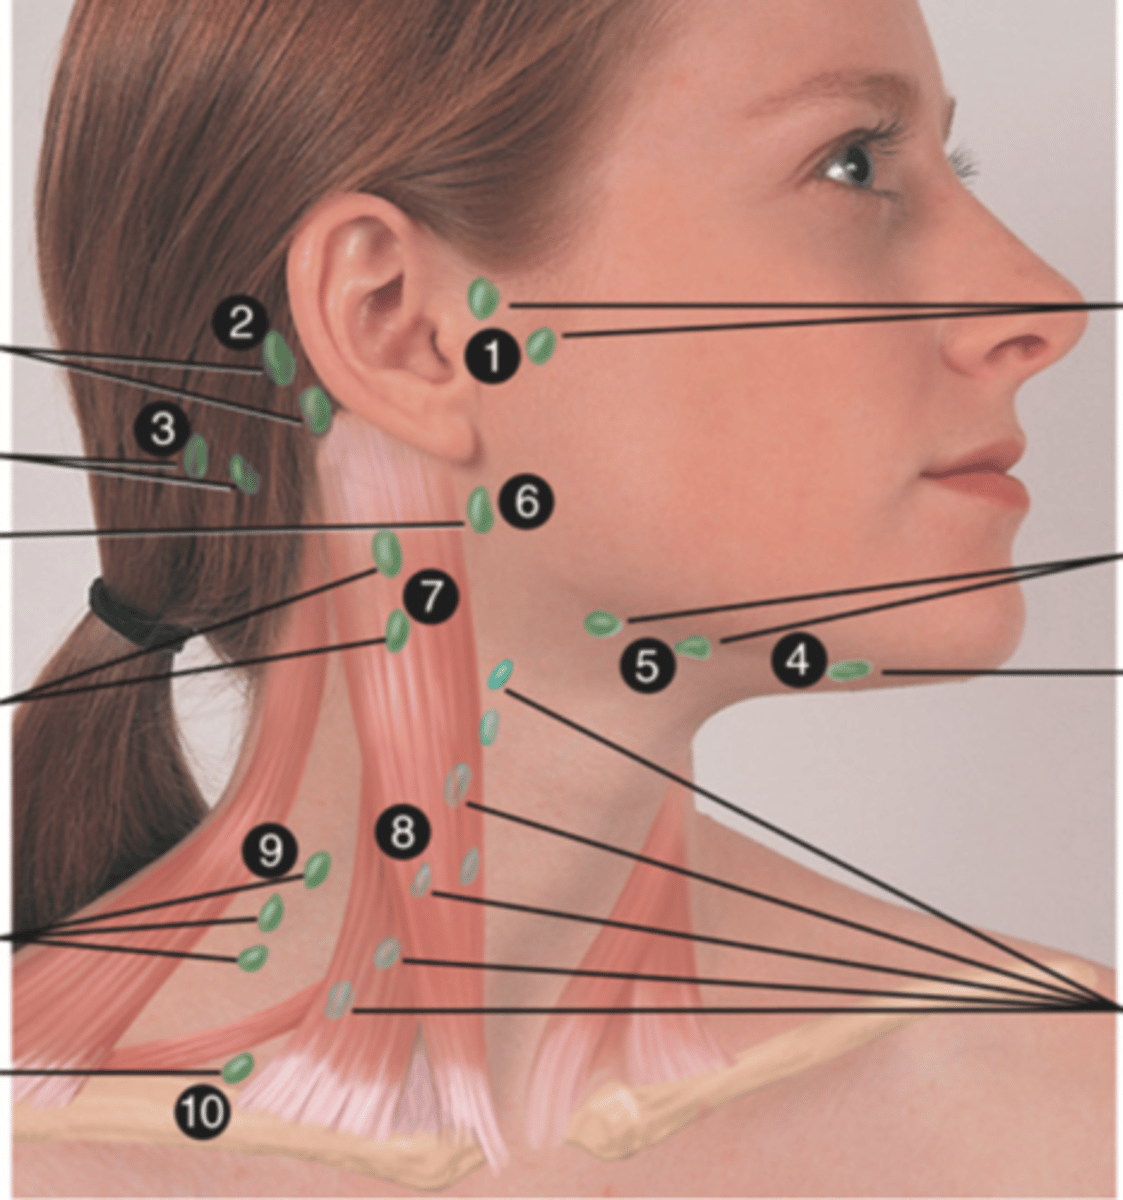

Major Lymph Nodes in the Neck (FUN!)

(Party People Often Sell Sardines Just So Dogs Pee Silver)

Preauricular Lymph Node

Lymph node in front of the ear (1)

Posterior Auricular Lymph Node

Lymph node behind the ear (2)

Occipital Lymph Node

Lymph node at the base of skull (3)

Submental Lymph Node

Lymph node under the chin (4)

Submandibular Lymph Node

Lymph node along base of mandible (5)

Jugulodigastric (Tonsil) Lymph Node

Lymph node under the angle of the mandible (6)

Superficial Cervical Lymph Node

Lymph node overlying the sternomastoid muscle (7); can feel enlarged even when there are no problems

Deep Cervical Chain Lymph Node

Lymph node located on the posterior triangle of the neck (8)

Posterior Cervical Lymph Node

Lymph node in the posterior triangle along the edge of the trapezius muscle (9)

Supraclavicular Lymph Node

Lymph node just above and behind the clavicle, at the sternomastoid muscle (10)